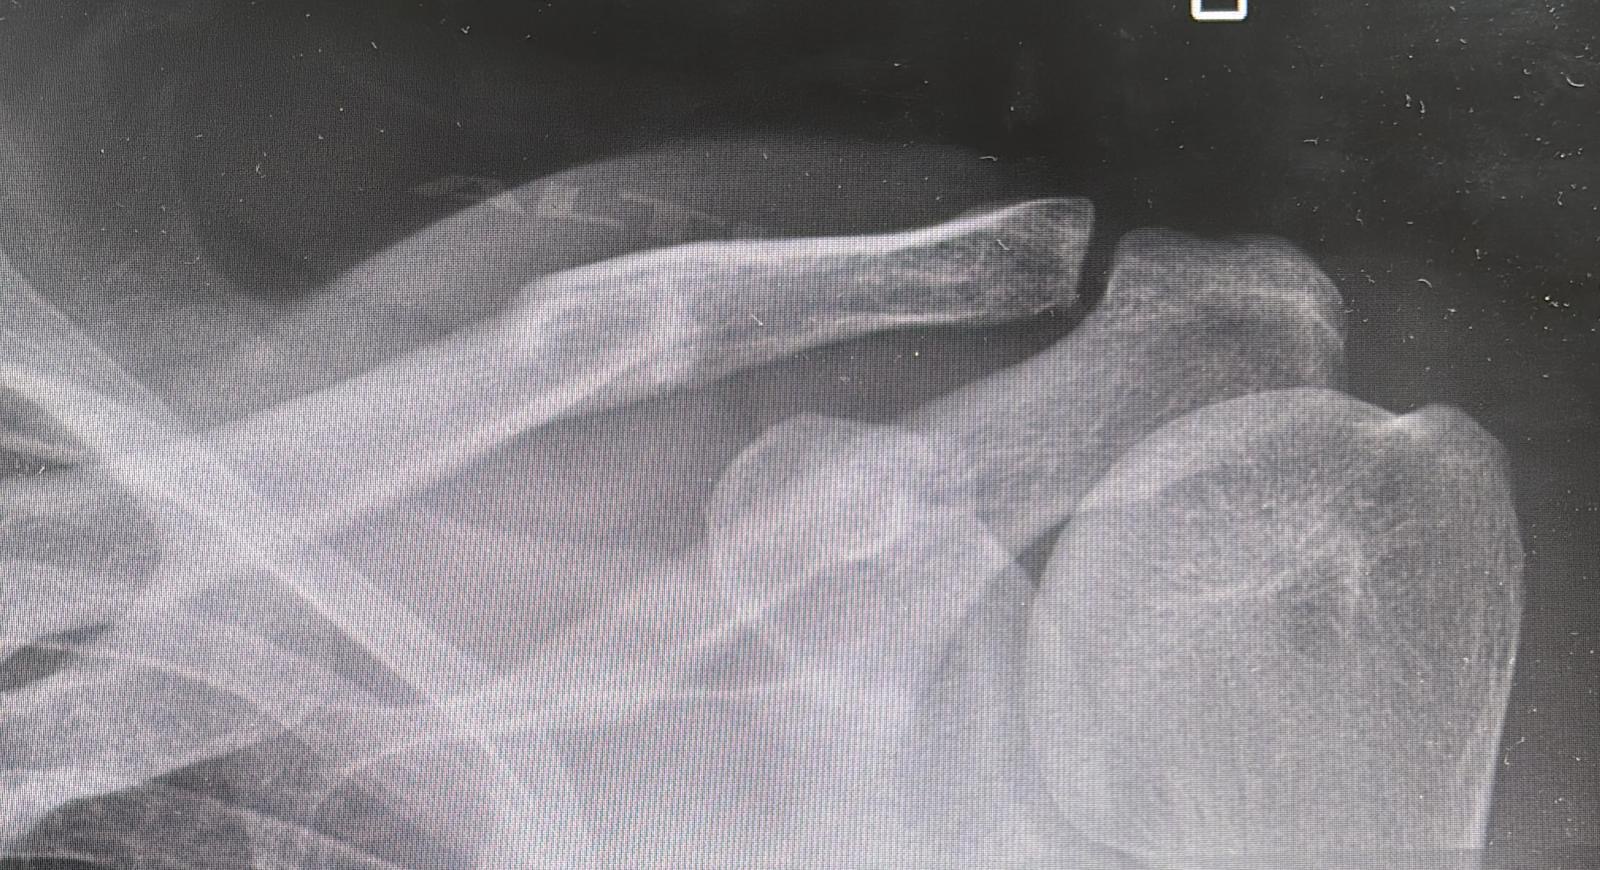

I fell off my bike in a training ride one week before the World Age Group Long Distance Triathlon Championships and fractured my clavicle. It was devastating to miss an event I’d trained so hard for, but the injury made racing impossible and recovery was the only sensible option.

It became clear straight away, once the fracture was confirmed by X-ray and my clinician advised no racing. Even though I knew it was fractured, I mentally needed the doc to tell me “no way mate”. With only a week to go, there was no realistic chance of competing, so I contacted Yellow Jersey to start the claim process.